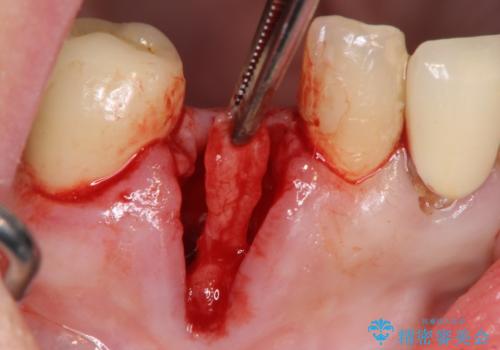

抜歯後、インプラントによる審美・機能改善を希望されたのでインプラント埋入に先立ち吸収した骨の再生を計画します。

歯を失う原因が虫歯や根尖病変などはなく、歯周病や歯の破折等周囲の骨を吸収する原因の場合はインプラント治療を行うに先立ち骨の造成が必要なことがあります。